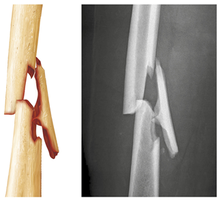

Fractures and Their Classification

Fractures are breaks in bone, commonly caused by trauma in youth and bone thinning in old age. They are classified by:

Position of bone ends: Nondisplaced (normal position) or displaced (misaligned).

Completeness of break: Complete (all the way through) or incomplete.

Penetration of skin: Open (compound) or closed (simple).

Epiphyseal | Epiphysis separates from diaphysis along growth plate. |